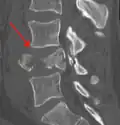

A burst fracture of L4 as seen on CT -